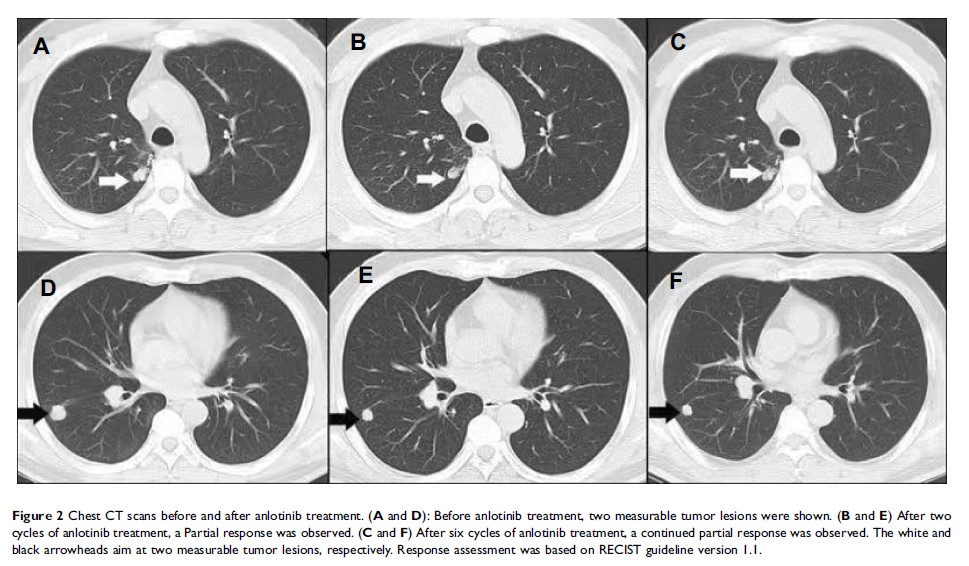

Case Report

- 作者:Shujie Song, Ping Sui, Minmin Li, Liangming Zhang, Dengjun Sun

- 期刊:OncoTargets and Therapy